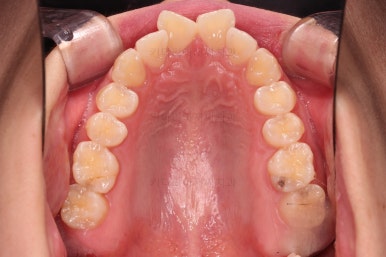

1. 초진

초진 시 입안의 모습입니다.

다만, 앞니ㅉㄱ이 공간이 부족해서 중간 치아들이 많이 회전되어있는데, 이를 환자분들의 표현에 따르면 "나비치아" 라고 부릅니다.

위아래 중간 앞니가 모두 나비치아처럼 되어있고요.